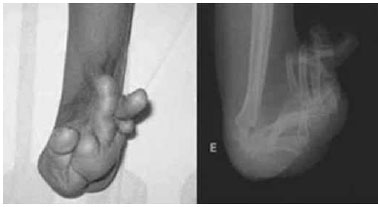

As deformidades consequentes às queimaduras variam desde a contratura de pele até a articular. A sinequia entre os espaços interdigitais é a mais comum, associada à hiperextensao das AMF e das interfalangeanas (AIF), em alguns casos estendendo-se ao punho, cotovelo e axila. No polegar observa-se a retraçao cutânea, fibrose e encurtamento do músculo adutor do polegar. Estas deformidades foram classificadas por Graham

1. Nos casos mais graves, as deformidades podem se estender para o punho (Figura 1), cotovelo e axila. A correçao cirúrgica quando a queimadura é grave, na maioria das vezes é complexa, e geralmente é necessária quando o atendimento inicial foi negligenciado ou insatisfatório. Muitos casos nao podem ser corrigidos com o tratamento conservador, sendo que uma ou mais intervençoes cirúrgicas sao necessárias, associada a um programa fisioterápico e uso de órteses ou próteses

Figura 1 - Deformidade grave de mao. Classificaçao grau IV.

A utilizaçao da classificaçao de Graham

1 e os achados do exame físico poderao auxiliar na avaliaçao pré-operatória se somente os procedimentos para o revestimento cutâneo forem suficientes ou se forem necessários procedimentos para liberaçao capsular e articular. As queimaduras mais graves do dorso da mao resultam em deformidade em garra com as AMF em extensao rígida e a articulaçao interfalangeana proximal (AIP) com contratura em flexao articular (Figura 1). Os procedimentos cirúrgicos foram indicados quando a fisioterapia e as órteses nao foram suficientes para recuperar a funçao dos membros superiores ou quando havia disfunçao funcional secundária a contratura cutânea, pobre excursao tendínea e subluxaçao articular. A avaliaçao pré-operatória foi necessária para indicaçao dos procedimentos, com a orientaçao dos passos cirúrgicos e a compreensao do paciente e familiares para acompanhar o tratamento reabilitador.